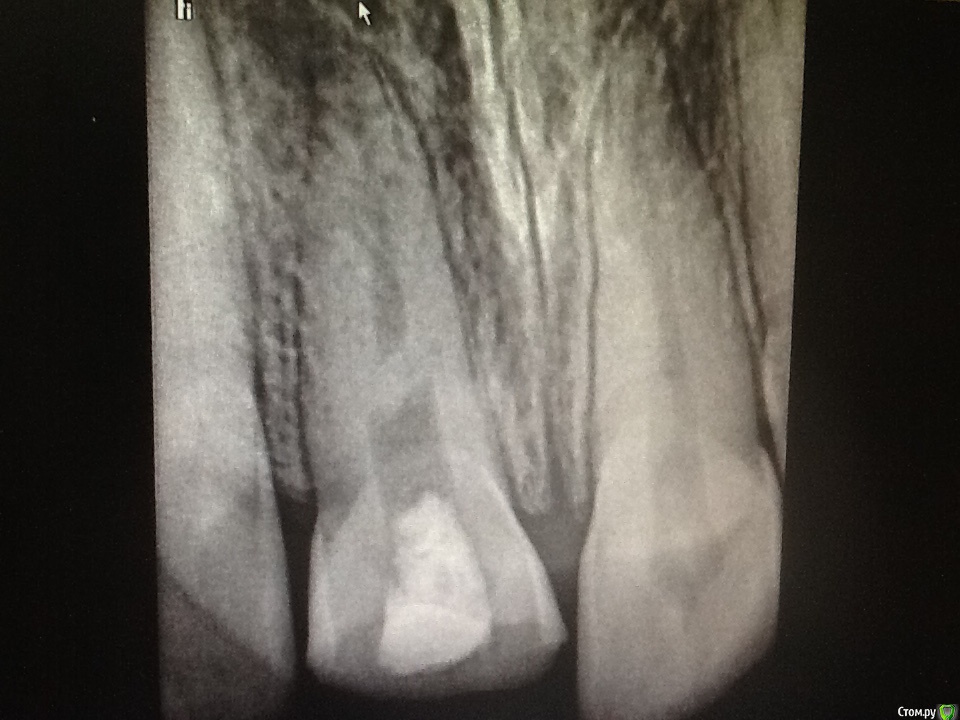

Л Ю С Я Опубликовано 8 октября, 2015 Поделиться Опубликовано 8 октября, 2015 Пациент получил травму в 6 летнем возрасте со вскрытием пульпы. 1.1 Явился в теч 6 часов. Со слов детского стоматолога( коллеги), сделала ампутацию пульпы, закрыли сицем. Ходил год, наблюдался, потом родители забили на это. Появились через 8 лет с просьбой сделать коронку емах, подростка беспокоил внешний вид)))) детский стоматолог начала работу, звонит мне, мол там камень, все ничего не могу сделать. Ссылка на комментарий

Л Ю С Я Опубликовано 8 октября, 2015 Поделиться Опубликовано 8 октября, 2015 И что там было в канале под дентином?Некротизированная пульпа с запашком Ссылка на комментарий

Каплан Опубликовано 8 октября, 2015 Автор Поделиться Опубликовано 8 октября, 2015 В мед каналах 3.6 происходит отложение заместит дентина. Ты уверен что воспаление там обратимо? Если потом придётся делать эндо, проблемы могут быть с прохождением каналов. Пульпа в апексе причём будет уже дохлая. Был недавно аналогичный случай у мальчика 14 лет. Травма в 6 лет возрасте, облитерация 1/3 канала, прислали на микроскоп. Я не могу сказать что было очень сложно. Но у детского стоматолога это вызвало проблемы. Могу показать снимок, если интересноДумаешь не стоит уже ждать закрытия апексов и сделать эндо? Ссылка на комментарий